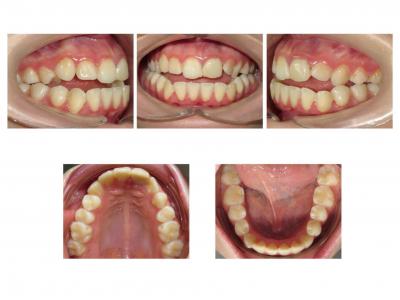

Voici les deux patientes traitées

Ici, dans les deux cas, les deuxièmes prémolaires ont été extraites et les traitements ont duré 18 mois.

Dans le premier cas, la béance s'est fermée spontanément (pas prévu au départ) sans rééducation, sans appareil de contrainte linguale, ni élastique. Il semblerait que le gain de place a permis aux incisives de se redresser spontanément et donc de fermer la béance. La fermeture de la béance, la normalisation de l'environnement anatomique a permis à la langue de se mettre à travailler correctement. Pour le sens transversal, la correction a été aussi spontanée. Juste une minivis dans le secteur 1 a été placée pour recentrer mon milieu (ancrage maximal recherché au départ). Les finitions auraient pu être meilleures. Elle finit avec une légère classe II (on va dire qu’elle est surcorrigée :)). Le traitement a terminé plus tôt que prévu (24 mois annoncé), car problèmes de santé.